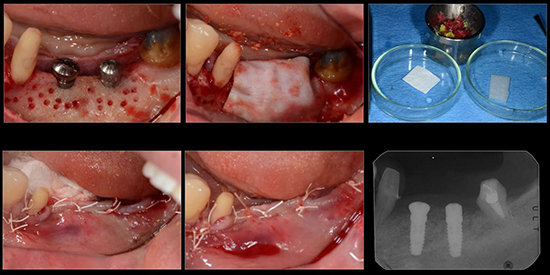

治療後01

治療後02

治療後03

治療後04